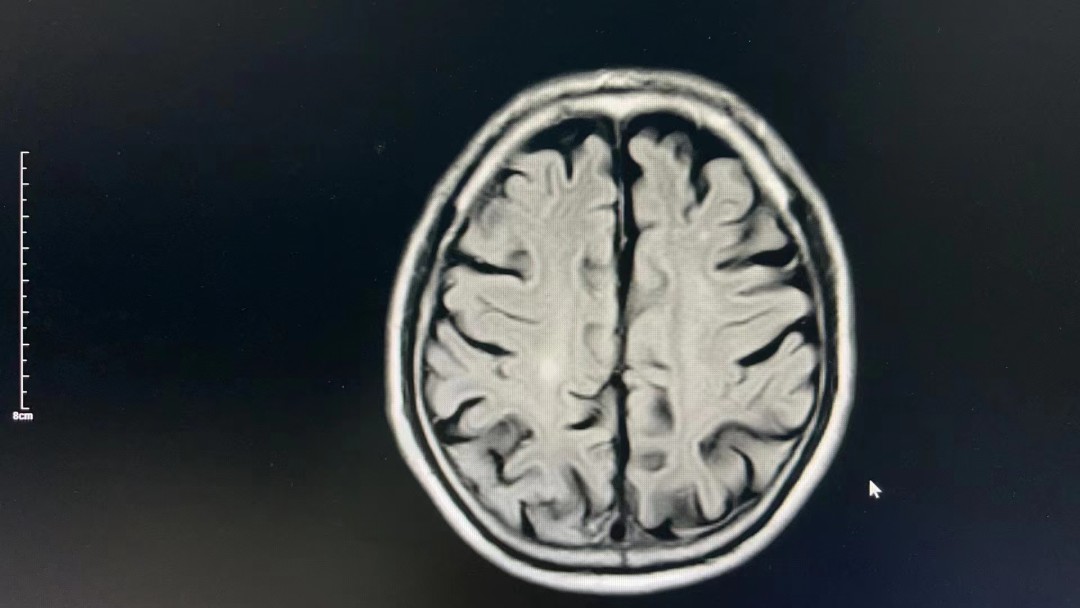

经了解,患者赵先生,68岁,主因“左侧肢体无力1.5小时”前来就诊。急诊科李志强主任经过诊查考虑患者可能为急性脑梗死,急需溶栓治疗。随后由急诊科医生带领患者查头颅CT、完善血化验等检查。经头颅CT结果回报,没有出血表现,考虑诊断为“急性脑梗死”。

患者后续收治到西医内科继续治疗,完善头颅核磁检查后考虑:“右侧大脑半球多发继续脑梗死”,此次治疗对患者远期生活质量获益较大,减少致残率,家属表示很感谢!